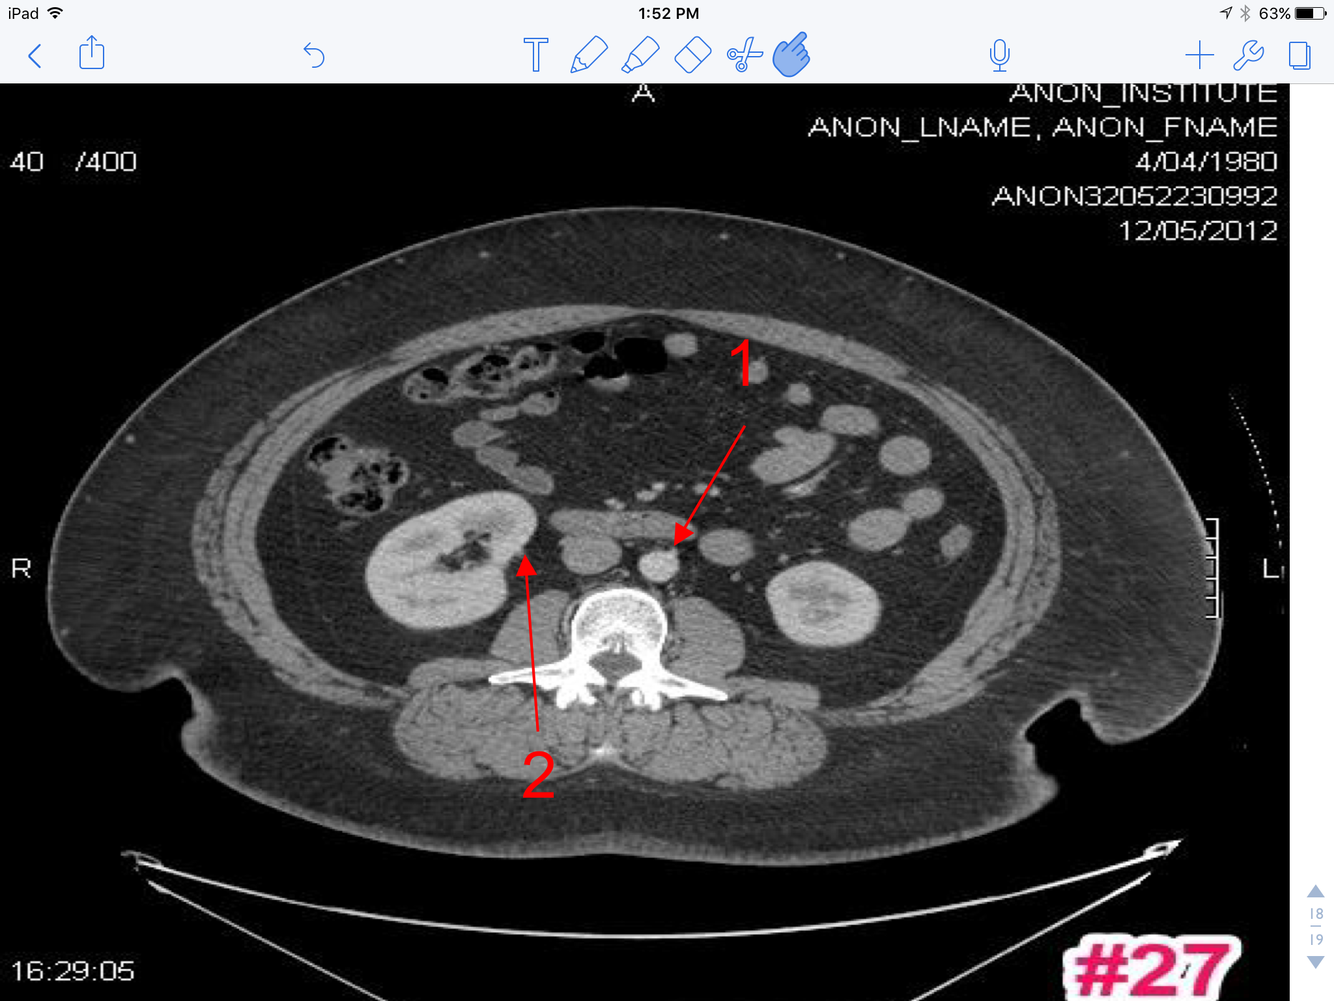

18

Q

A

1. Inferior mesenteric A

2. Cecum of colon

3. Lower pole of the Lt. kidney